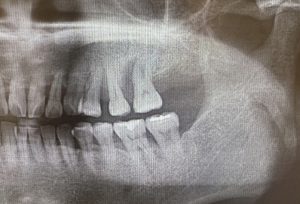

治療前レントゲン

歯の周りの骨がなくなり、レントゲンで黒くうつっている。